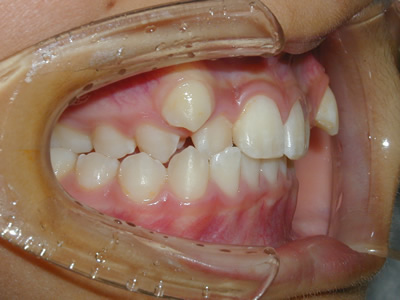

永久歯に交換するためのスペース不足による前歯のガタガタで、取り外しができる拡大床にて上下顎の幅を拡大した後、上顎の前歯をマルチブラケット装置で並べました。治療の期間は1年9か月でした。

初診時